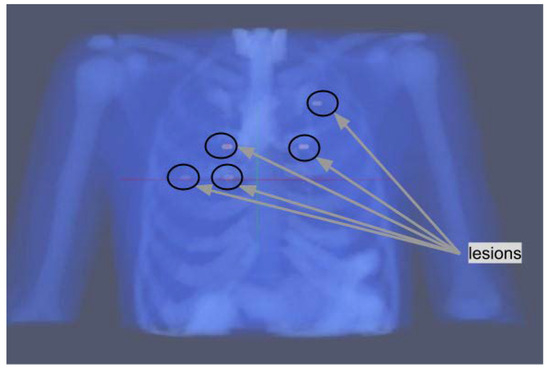

In order to assess the performance of the proposed algorithms, synthetic projection data have been generated from the digital 4D extended cardiac-torso XCAT phantom [14] in which five lesions have been added.

Their position is shown in Figure 1; two lesions are localized in slice 55, two lesions in slice 65, and one lesion in slice 80. The rationale for their positioning is described in the following. One of the lesions is placed in the upper part of the lungs, this should be the easiest one to detect as respiratory motion is lower in that region. Two of them are placed in proximity to the heart, which has an high uptake through the blood pool, and are therefore expected to have a lower contrast compared to their surroundings. The remaining two lesions are placed around the middle of the lungs, one on each side.

Figure 1. Position of the five lung lesions in the XCAT phantoms.